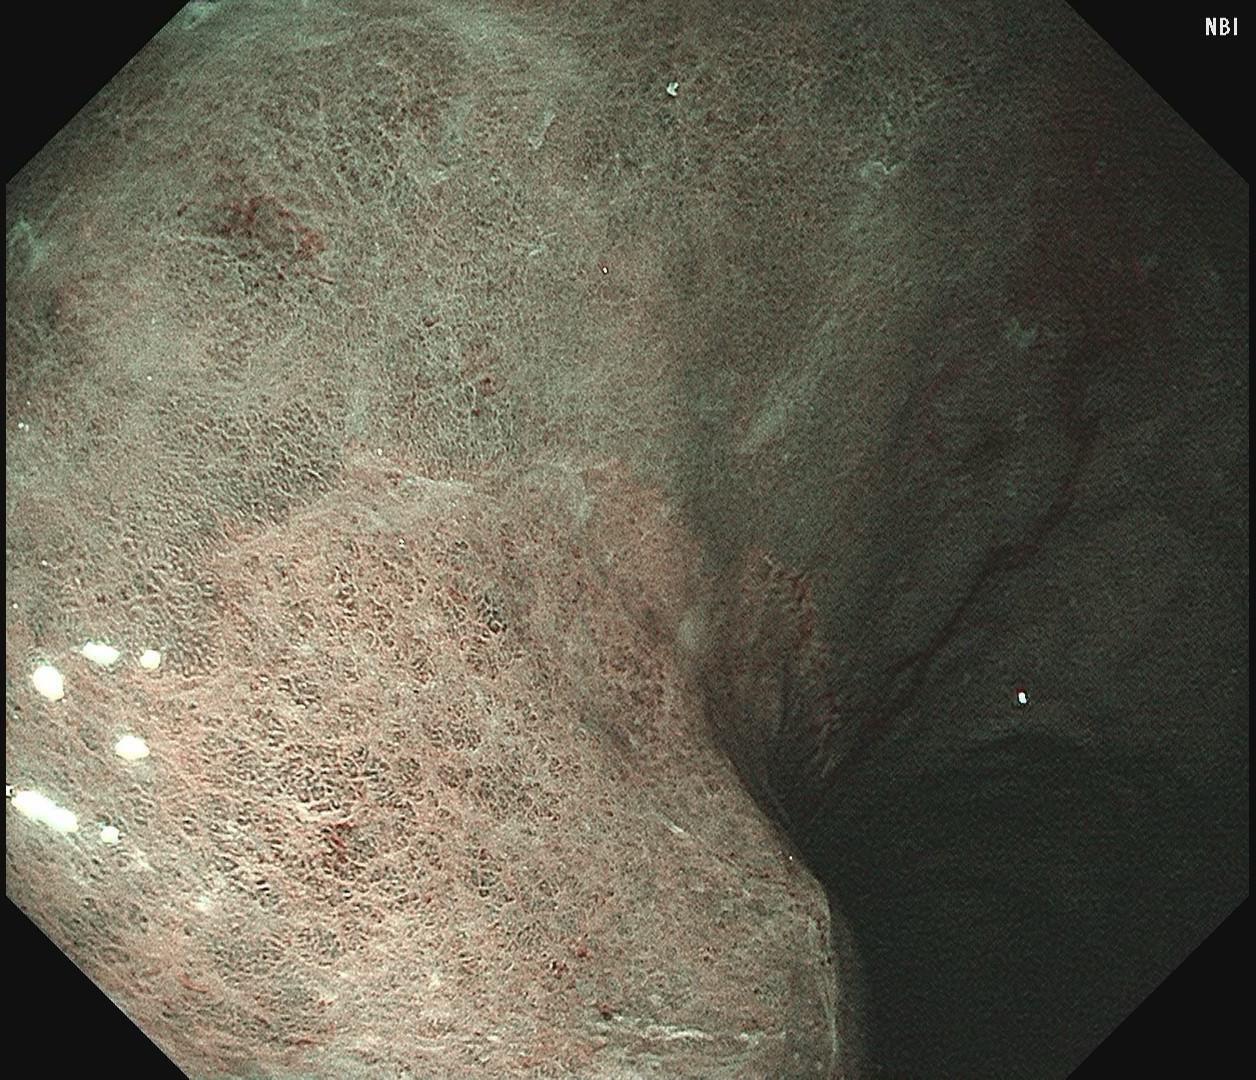

男,61岁,胃巨大褪色调病变。答案在最后一张图片,你猜对了吗? 患者因上腹部饱胀行胃镜检查,Hp阴性背景,胃窦至贲门下见一巨大褪色调病变,边界清晰,病变相对表浅,未见明显溃疡及隆起,胃壁较柔软,充气顺应性佳,予多点活检确诊,拟外科手术行全胃切除。做这么多年胃镜,还是第一次遇到这样的……